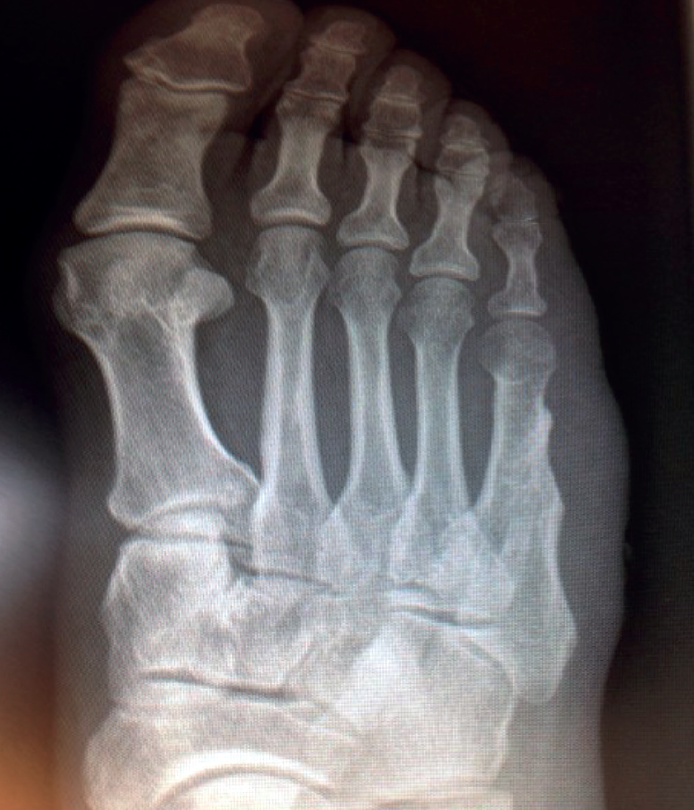

rpt.3702.fs2303007-figura2.png

Figura 2. Imagen radiológica de duplicación del quinto metatarsiano.

El examen físico (Figura 1) reveló la presencia de un dedo supranumerario y en la radiografía (Figura 2) de control se apreciaba una duplicación parcial del quinto metatarsiano, en forma de “Y”. La hemos clasificado como polidactilia postaxial utilizando la clasificación de Venn-Watson.